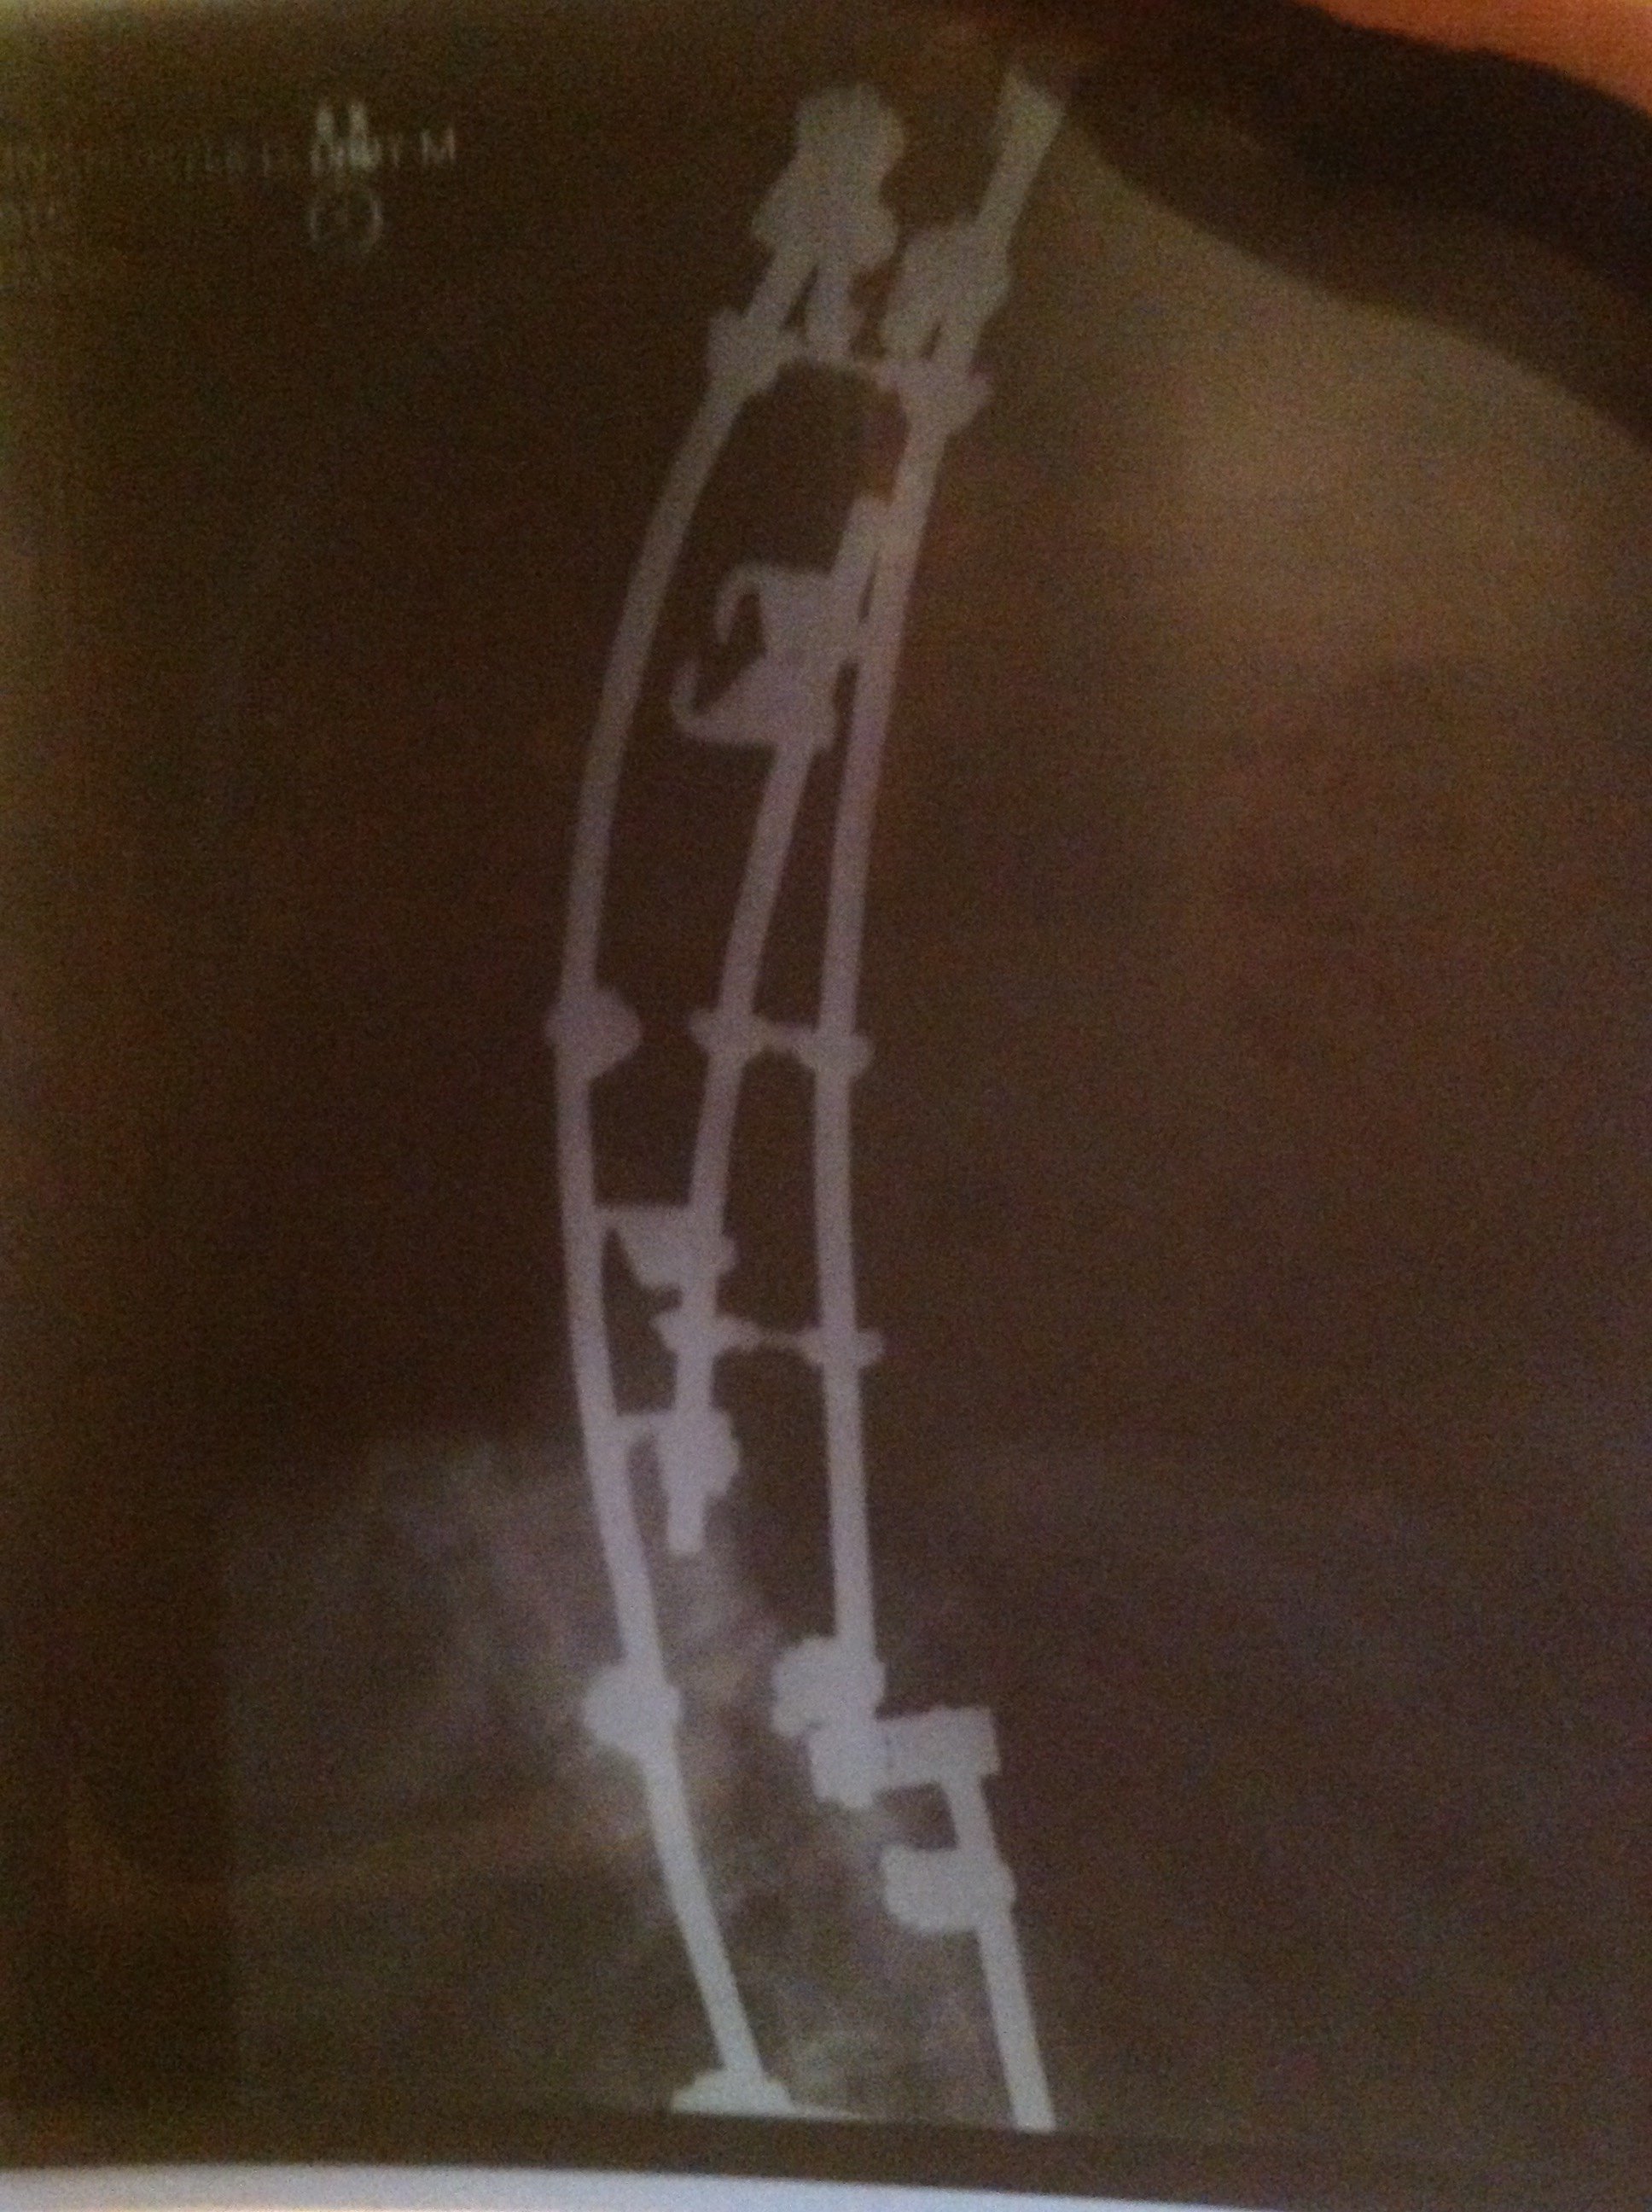

Yul Lose Posted February 1 Posted February 1 Best of luck to you. Times and procedures have changed a lot since my first 12 vertebrae were done in 1979 and 21 vertebrae, including the first 12 were fused and instrumented in 1992. I was in a body cast in 1979 for 4 months and then a back brace for 18 months after that. In 1992 I had so many complications that they put me in a medically induced coma for 2 months. They cleaned out the old fusions and discs and the other 9 discs and were going to go in the next day and do the fusions and install the hardware but I started having breathing issues and they couldn’t go back in to finish up for 5 months. So I laid in bed in a kydex jacket trying to get strong enough for them to finish. I was tube fed for nearly 3 months and had to learn how to talk, swallow and walk again. Both of the latter procedures were anterior and posterior approaches so they opened me up from tail bone to neck and across my abdomen both times. Recovery took many months. A lady that I shoot with just had 11 vertebrae done and her recovery was much faster. My surgeon told me that between my side to side and front to back curvature (scoliosis) I had 94 degree curvature, he said it was the worst he'd ever attempted to repair. Listen to and follow all of the advice that your surgeon and therapists give you, you’ll be glad you did. My X-rays. 1 2 Quote

Texas Maverick Posted February 1 Author Posted February 1 1 hour ago, Yul Lose said: Best of luck to you. Times and procedures have changed a lot since my first 12 vertebrae were done in 1979 and 21 vertebrae, including the first 12 were fused and instrumented in 1992. I was in a body cast in 1979 for 4 months and then a back brace for 18 months after that. In 1992 I had so many complications that they put me in a medically induced coma for 2 months. They cleaned out the old fusions and discs and the other 9 discs and were going to go in the next day and do the fusions and install the hardware but I started having breathing issues and they couldn’t go back in to finish up for 5 months. So I laid in bed in a kydex jacket trying to get strong enough for them to finish. I was tube fed for nearly 3 months and had to learn how to talk, swallow and walk again. Both of the latter procedures were anterior and posterior approaches so they opened me up from tail bone to neck and across my abdomen both times. Recovery took many months. A lady that I shoot with just had 11 vertebrae done and her recovery was much faster. My surgeon told me that between my side to side and front to back curvature (scoliosis) I had 94 degree curvature, he said it was the worst he'd ever attempted to repair. Listen to and follow all of the advice that your surgeon and therapists give you, you’ll be glad you did. My X-rays. All I can say is wow, glad it has all worked out for you. TM 1 Quote